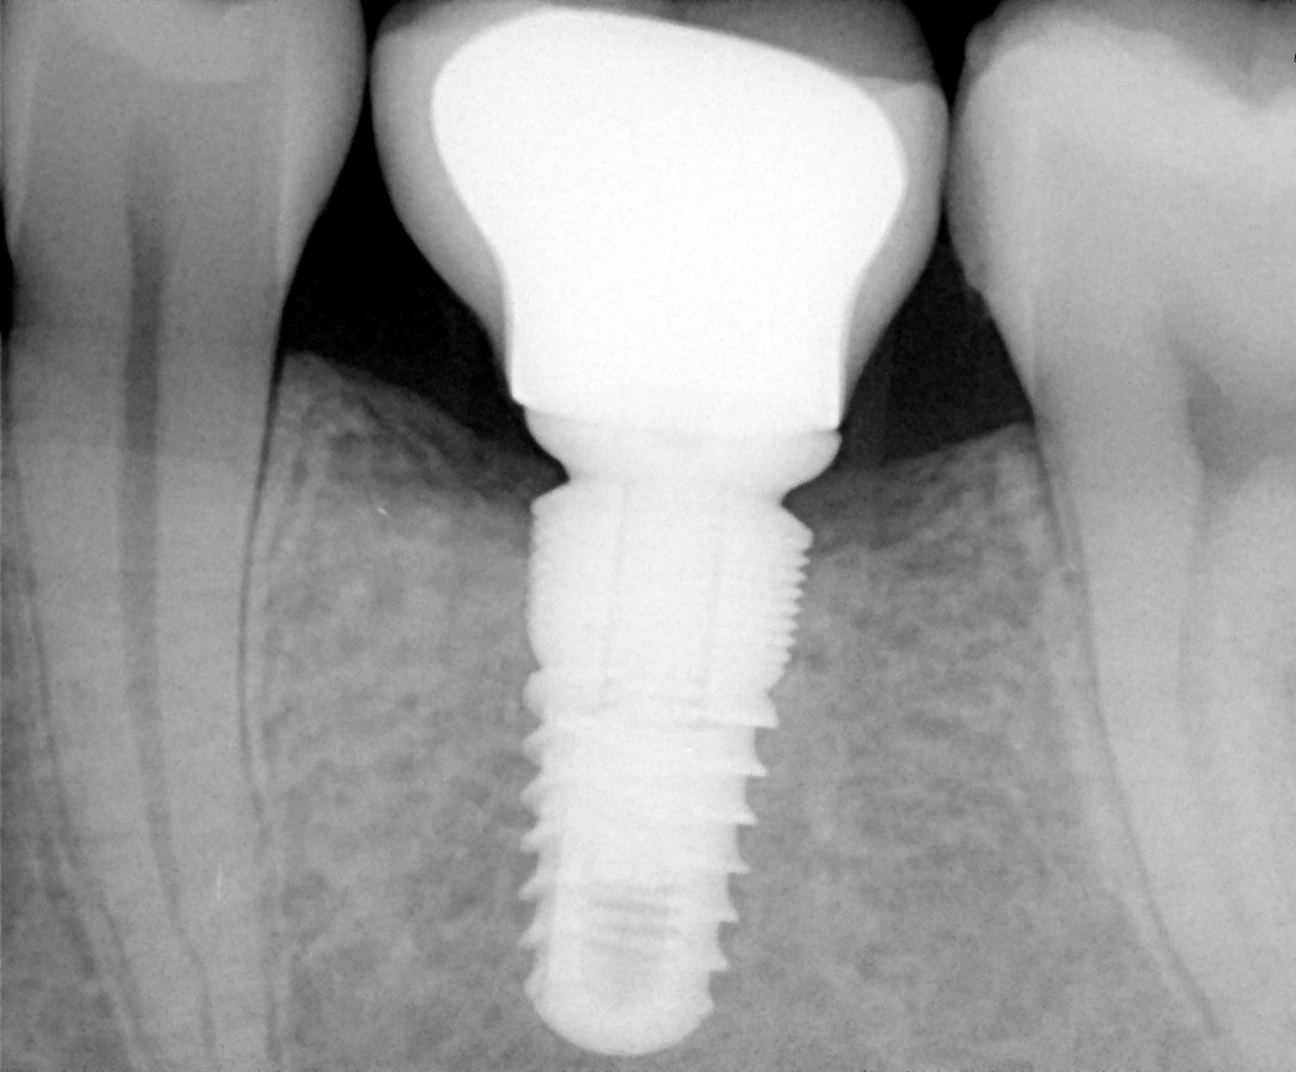

Nowoczesna stomatologia daje pacjentom doskonałe rozwiązanie problemu braków zębowych. Z pomocą przychodzą bowiem implanty stomatologiczne — rozwiązanie bardzo zbliżone do naszych naturalnych zębów. Pozwalają doskonale odtworzyć funkcję i estetykę utraconych zębów. Implanty stomatologiczne to tytanowe śruby, które zastępują korzeń zęba. Implantolog wkręca implant stomatologiczny w miejsce utraconego zęba, a dokładnie w kość szczęki lub żuchwy, by po kilku miesiącach osadzić na nich wykonaną w laboratorium protetycznym koronę.

Szablony implantologiczne, najprościej ujmując, to specjalistyczne nakładki z otworami stosowane w nawigowanej implantologii. Podczas zabiegu wszczepienia implantu przykłada się do łuku zębowego pacjenta taką nakładkę, której otwory dokładnie wskazują operatorowi, w jakim miejscu i pod jakim kątem u danego pacjenta ma być umieszczony implant stomatologiczny. Stworzenie takiego szablonu poprzedza szczegółowa analiza obrazu tomografii komputerowej CBCT, która pozwala na zaplanowanie pozycji, rozmiaru i kształtu implantu. Po tym etapie implantolog zleca w laboratorium wydruk szablonu, który będzie potrzebny podczas samego zabiegu.